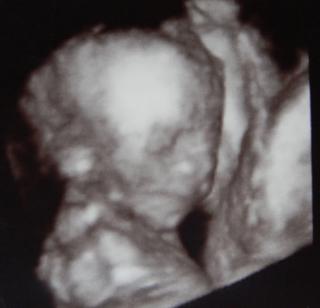

aj my se tesime 3D🙂tentokrat si reknu aj o 3D fotku u dr, alebo mi ukazovala babulo aj 3D, ake fotku jsem si dala CB....